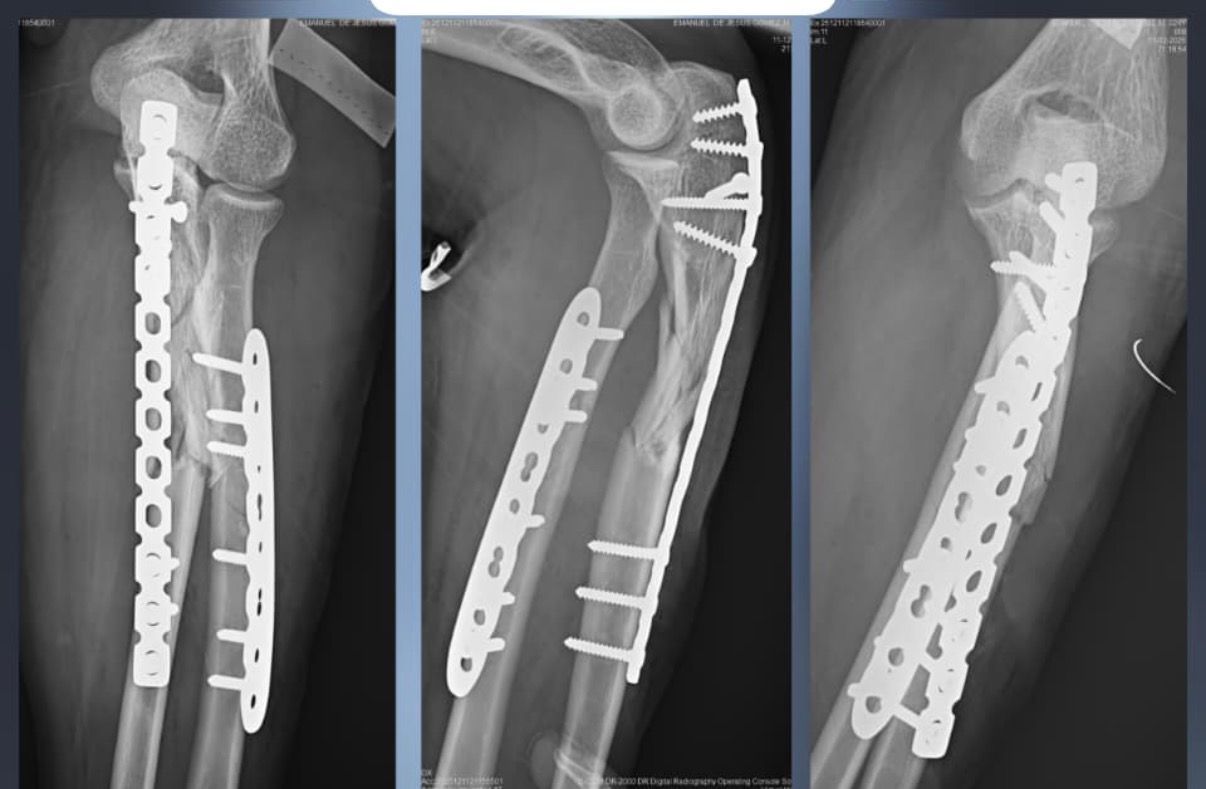

Fotos y videos